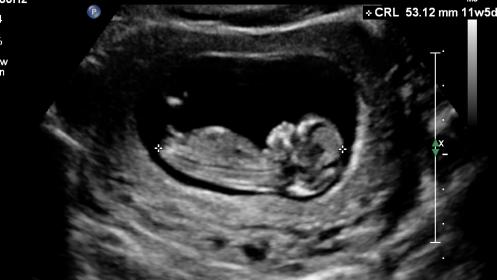

Hi everyone, i have a looong wait til getting comfirmation of gender (20 wk scan, im 14wks today)

Your guesses are appreciated muchly !

Maybe boy

Boy

The angle of dangle points UP and in the crotch shot there shouldn't be anything there! BOY!

Fantastic thanks for the info! Hoping for a boy too!